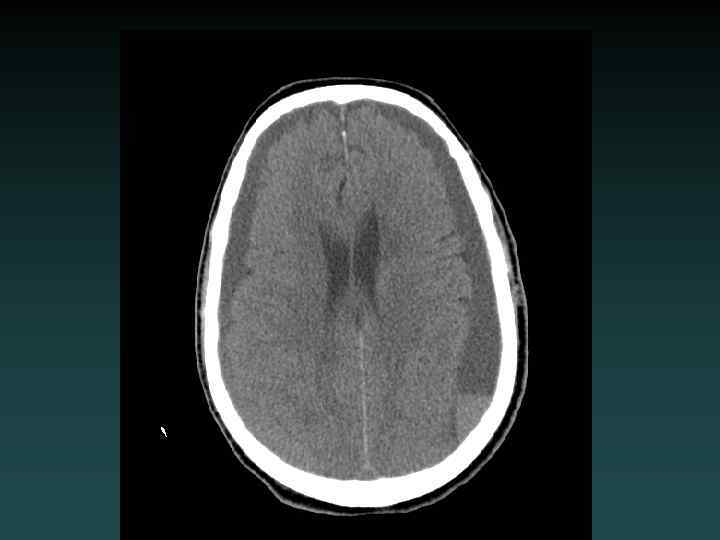

Chronic Infarction • VOLUME LOSS – Ex vacuo dilatation • Hypodensity – encephalomalacia